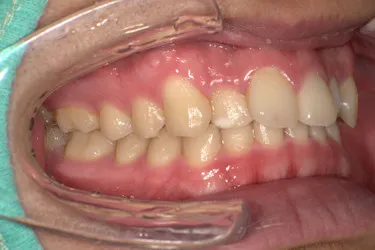

歯並びがコンプレックスで友人と写真を撮る際も気にしてしまっていたという20歳の男子大学生I.T.様にのI.T.様。始めやすい価格と目立ちにくさからスマイルモア矯正を選び、自信を持って笑えるようになった経緯を伺いました。

| 治療内容 | マウスピースを用いた歯列矯正 |

| 追加処置 | IPR |